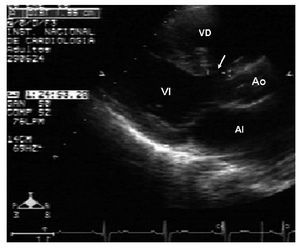

Figura 2 Ecocardiograma en eje paraesternal largo bidimensional donde se observa la medición de la comunicación interventricular. AI: aurícula izquierda; Ao: aorta; VD: ventrículo derecho; VI: ventrículo izquierdo.